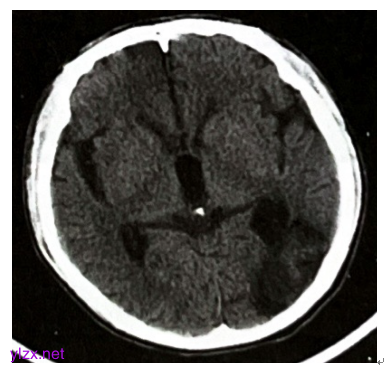

2024年2月23日颅脑CT示左侧枕叶及左侧侧脑室旁脑出血吸收后局部软化(图4)。

图4 颅脑CT